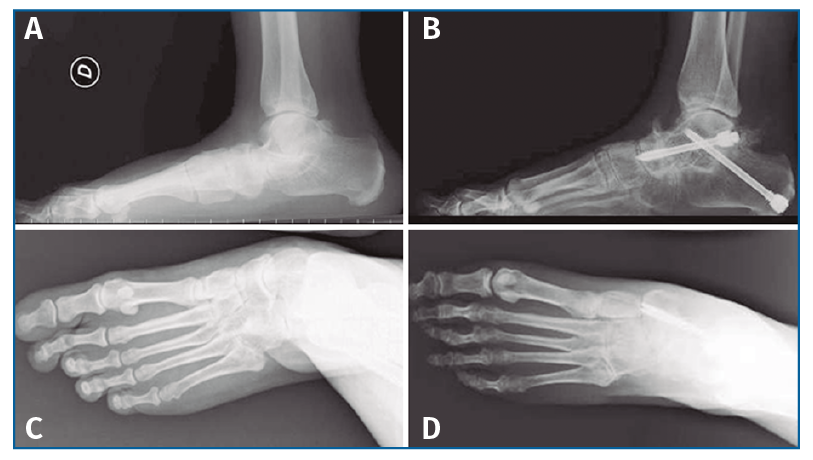

Figura 6. Aspecto radiográfico pre- (A y C) y postoperatorio (B y D) mostrando la corrección de las mediciones angulares.

El ángulo AP talo-calcáneo presentó una mejoría media de 13,42° desde 28,96° en preoperatorio a 15,54° en el postoperatorio. El ángulo AP talo-primer metatarsiano mejoró 15,87° desde una media preoperatoria de 24,37° a 8,5° de media en el postoperatorio. El ángulo AP de cobertura de astrágalo presentó una mejoría media de 35,28° desde 36,35° en preoperatorio a 1,07° en el postoperatorio. El ángulo lateral talo-calcáneo mejoró 19,74° desde una media preoperatoria de 52,54° a 32° de media en el postoperatorio. El ángulo lateral talo-primer metatarsiano presentó una mejoría media de 23,71° desde 25,37° en preoperatorio a 1,66° en el postoperatorio. El ángulo calcaneal pitch mejoró 3,72° desde una media preoperatoria de 12° a 15,72° de media en el postoperatorio.